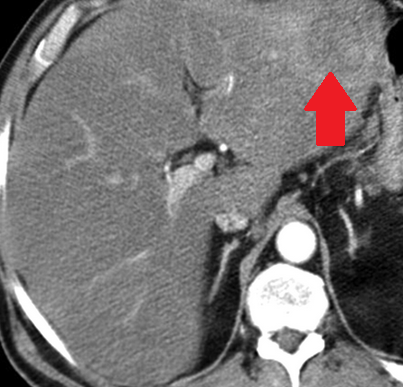

Αυτόματη ρήξη/αιμορραγία νεφρού — αγγειομυολίπωμα (Ευγενική παραχώρηση Dr. V. Penopoulos)